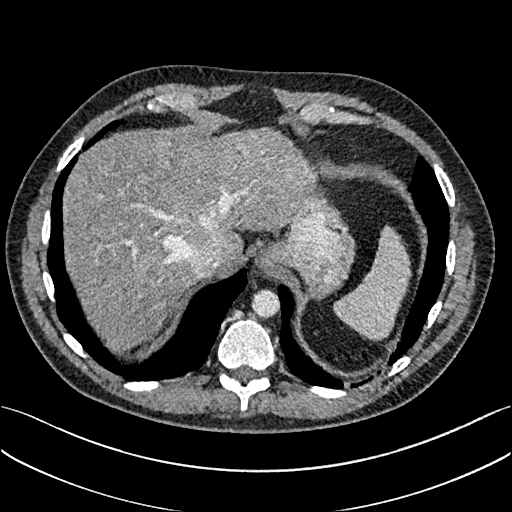

To demonstrate the effectiveness of the proposed network, we perform the qualitative comparisons over three representative abdominal images presented in Figs. 3, 5 and 7. For better evaluations of the image quality with different denoising models, zoomed regions-of-interest (ROIs) are marked by red rectangles and shown in Figs. 4, 6 and 8 respectively. Note that all results from different denoising models focus on two aspects: content restoration and noise-reduction. All CT images in axial view are displayed in the angiography window [-160, 240]HU.

The real NDCT images and corresponding LDCT images are presented in Figs. 3a and 3b. As observed, there are distinctions between ground truth (NDCT) images and LDCT images. Figs. 3a and 7a show the lesions/metastasis. Fig. 5a presents focal fatty sparing/focal fat. In Figs. 4a, 6a and 8a, these lesions can be clearly observed in NDCT images; in contrast, from Figs. 4b, 6b, and 8b, it can be seen that the original LDCT image is noisy, and lacks structural features for task-based clinical diagnosis. All adopted denoising models suppress noise to some extent.

Mean-based methods can effectively reduce noise, but the side effect is impaired image contents. In Fig. 3c, -net greatly suppresses the noise, but blurs some crucial structural information in the porta hepatis region. Meanwhile, some waxy artifacts can still be observed in Fig. 6c. -net does not produce good visual quality because it assumes that the noise is independent of local characteristics of the images. Even though it retains high SNR, its results are not clinically preferable. Compared with -net, in Figs. 3d and 5d, it can been seen that -net encourages less blurring and preserves more structural information. However, as observed in Fig. 4d, it still over-smooths some anatomical details. Meanwhile, in Fig. 6d, there are some blocky effects marked by the blue arrow. The results obtained by RED-CNN [35] deliver high SNR but blur the vessel details as shown in Figs. 4i and 6i.

For SL-based methods, as observed in Figs. 3e and 5e, SL-net generates images with higher contrast resolution and preserves texture of real NDCT images better than -net and -net. However, Figs. 4e and 6e show that SL-net does not preserve the structural features well, and there still remain small streak artifacts. Subsequently, in Figs. 4e and 4f, SL-net and MSL-net have low frequency image intensity variance because SSIM/MS-SSIM is insensitive to uniform biases [49, 51]. On the other hand, -net preserves the overall image intensity, but it does not preserve high contrast resolution well as SL-net and MSL-net do.

From Figs. 7 and 8, we can see mean-based and SL-based methods work well with effective noise suppression and artifact removal. However, the illustrations in Fig. 8 show that these methods blur the local strutural features. Our proposed SMGAN-based methods present a better edge preservation than the competing methods.

Overall, the observations above support the following statements. First, although the voxel-wise methods show good noise-reduction properties, to some extent they blur the contents and lead to the loss of structural details because they optimize the results in the voxel-wise manner. Second, SL-based methods better preserve texture than mean-based methods, but they cannot preserve overall image intensity. Third, the results produced by the proposed SMGAN-3D demonstrate the benefits of the combination of two loss functions and the importance of the adversarial training [41, 42].